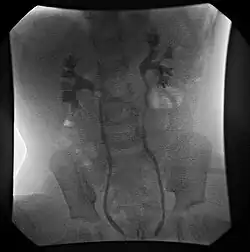

![]() | |

| Ultrasound image showing abnormal vesicoureteral junction and dilated distal ureter resulting in primary vesicoureteral reflux (VUR). | |